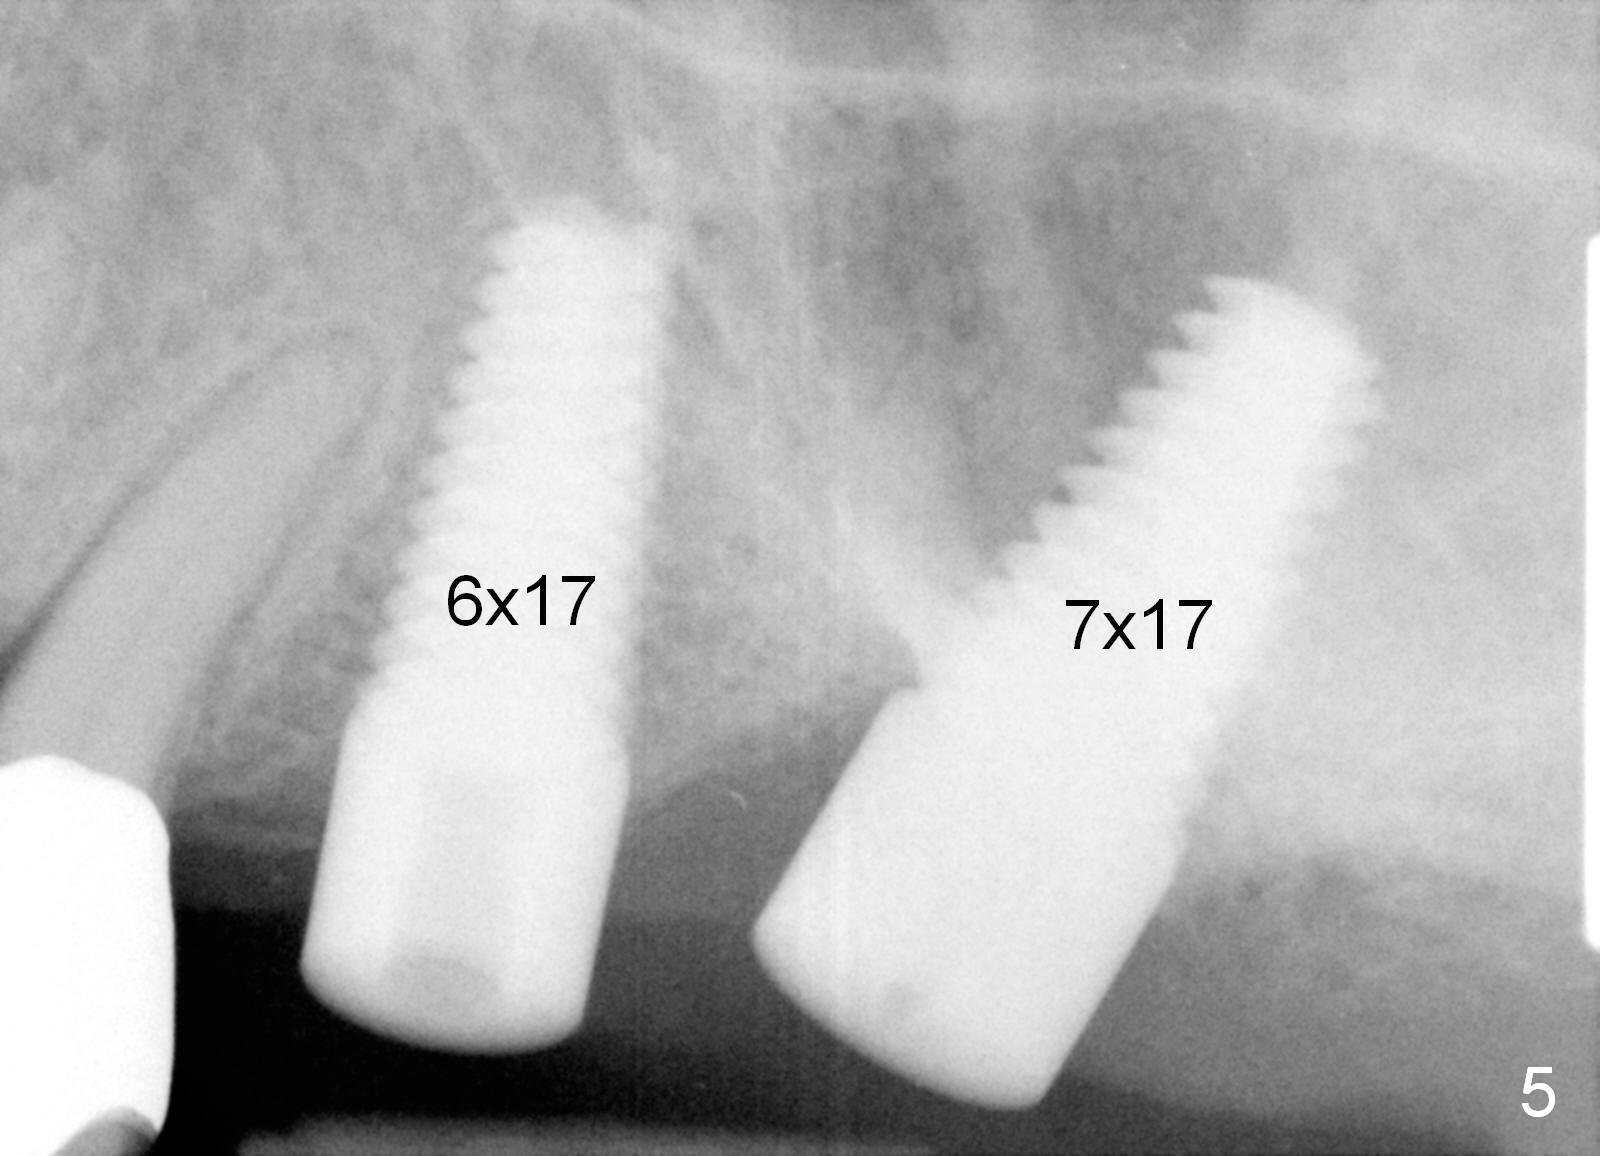

A 58-year-old man used to have a upper left 3-unit bridge. Two months after extraction and immediate implant at the site of the posterior abutment, an implant is planned to be placed at the site of the pontic, #14 (Fig.1). Osteotomy starts with a 1.6 mm pilot drill, followed by bone expanders, parallel to the crown of the tooth #13. The first intraop PA shows that 3.0 mm bone expander is close to the root of the neighboring tooth (Fig.2). No matter what is done to change the trajectory of the osteotomy using expanders according to the crown morphology of the neighboring tooth, the next 3 expander does not improve in parallelism (Fig.3). When a 6x17 mm tap is inserted (Fig.4 T), it is realized that axis of the tap is parallel to the axis of the crown of the neighboring tooth (black line), but not that of the root (red line). It is too late to change the trajectory drastically; a 6x17 mm implant is placed with insertion torque > 60 Ncm (Fig.5). It is best to change the trajectory as early as possible, e.g., after taking the first intraop PA and withdrawing the expander (Fig.6 black area) and as much as possible (red line; starting new osteotomy). It is quite similar to immediate implant. There is no bone loss 2 months postop (Fig.7), 18 months (Fig.8,9) or 34 months (Fig.10)post cementation, in spite of open contact between the crowns (Fig.10 black arrowhead). This is partially due to supragingival margin (Fig.11,12 (immediately pre-cementation)). No bone loss is noted 3 years 5 months post cementation (Fig.13).